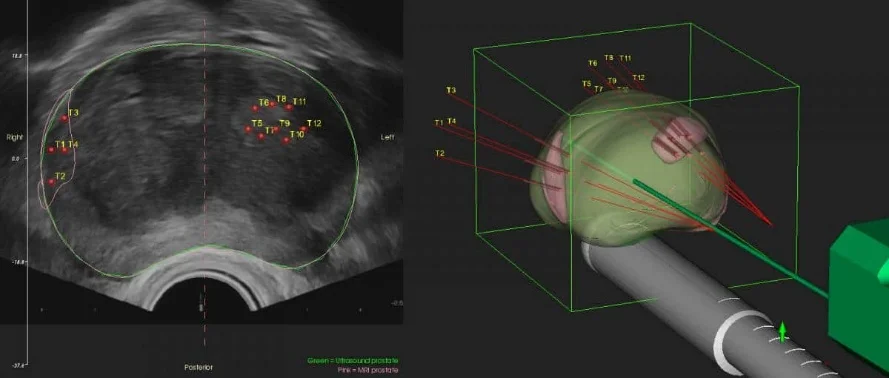

Οι εικόνες της μαγνητικής τομογραφίας με ένα ειδικό λογισμικό μεταφέρονται στο σύστημα υπερήχου (σύντηξη = fusion), με το οποίο διενεργείται η στοχευμένη fusion βιοψία προστάτη.